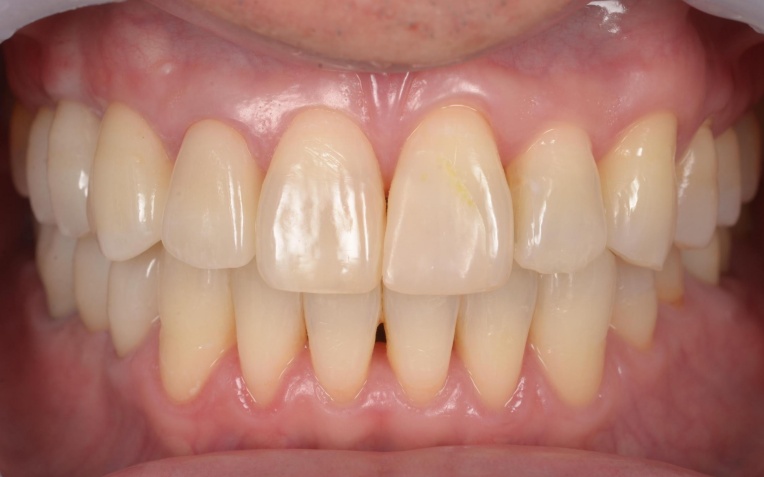

矯正治療終了後は、整えた歯並びが後戻りしないよう、細いワイヤーを固定して歯並びを安定させる装置「リテーナー」を装着しました。

その後、小樽山岡デンタルオフィスにてインプラント治療と被せ物の治療を行い、治療を終了しています。

治療後